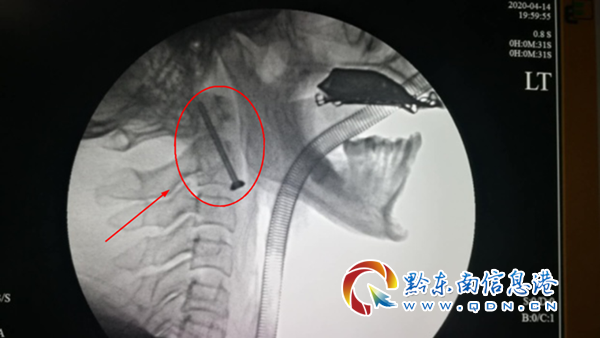

術后X線側面影像圖

“樞椎齒狀突”骨折分為三型,其中Ⅱ型骨折不愈合率為15%-85%。患者診斷結果明確后,貴醫大二附院骨一科團隊組織進行了討論,討論決定此次手術采用前路齒狀突骨折螺釘內固定手術將骨折的解剖復位和穩定的螺絲釘內固定相結合,符合AO/ASIF小組建立的原則。該術式既能夠保留寰樞椎旋轉功能,提高骨折愈合率,術后又不需加強外固定。于4月14日下午為患者實施了手術。